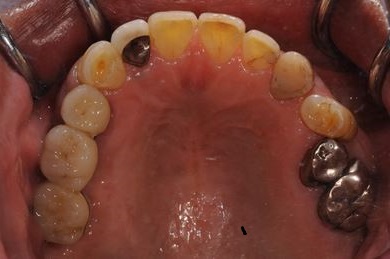

インプラントの症例写真 IMPLANT

骨再生インプラント治療+セラミック治療

| 性別/年齢 | 男性 / 60歳 | ||||||||||||||||||||||||||||||||

| 主訴 | 右上奥歯が動いて痛みがある。 | ||||||||||||||||||||||||||||||||

| 治療内容 | インプラント5本(サイナスリフト、GBR)、ハイブリッドセラミッククラウン5本、メタルボンドセラミッククラウン1本(メタルボンド用土台1本)、ハイブリッドセラミックインレー、遊離歯肉移植手術 | ||||||||||||||||||||||||||||||||

| 治療期間 | 1年7ヶ月 |